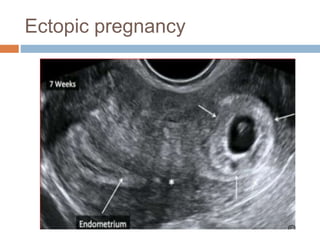

Ectopic pregnancy